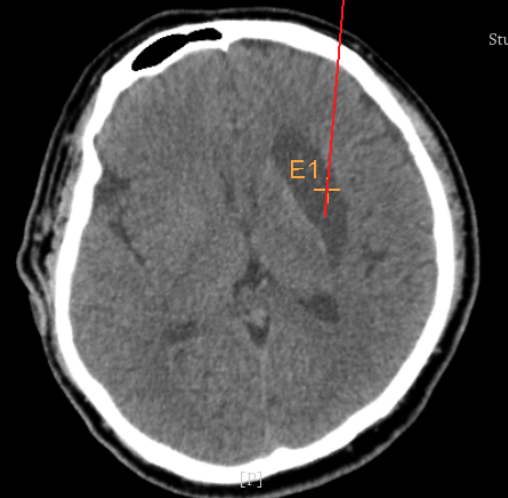

術(shù)后CT:血腫腔消失